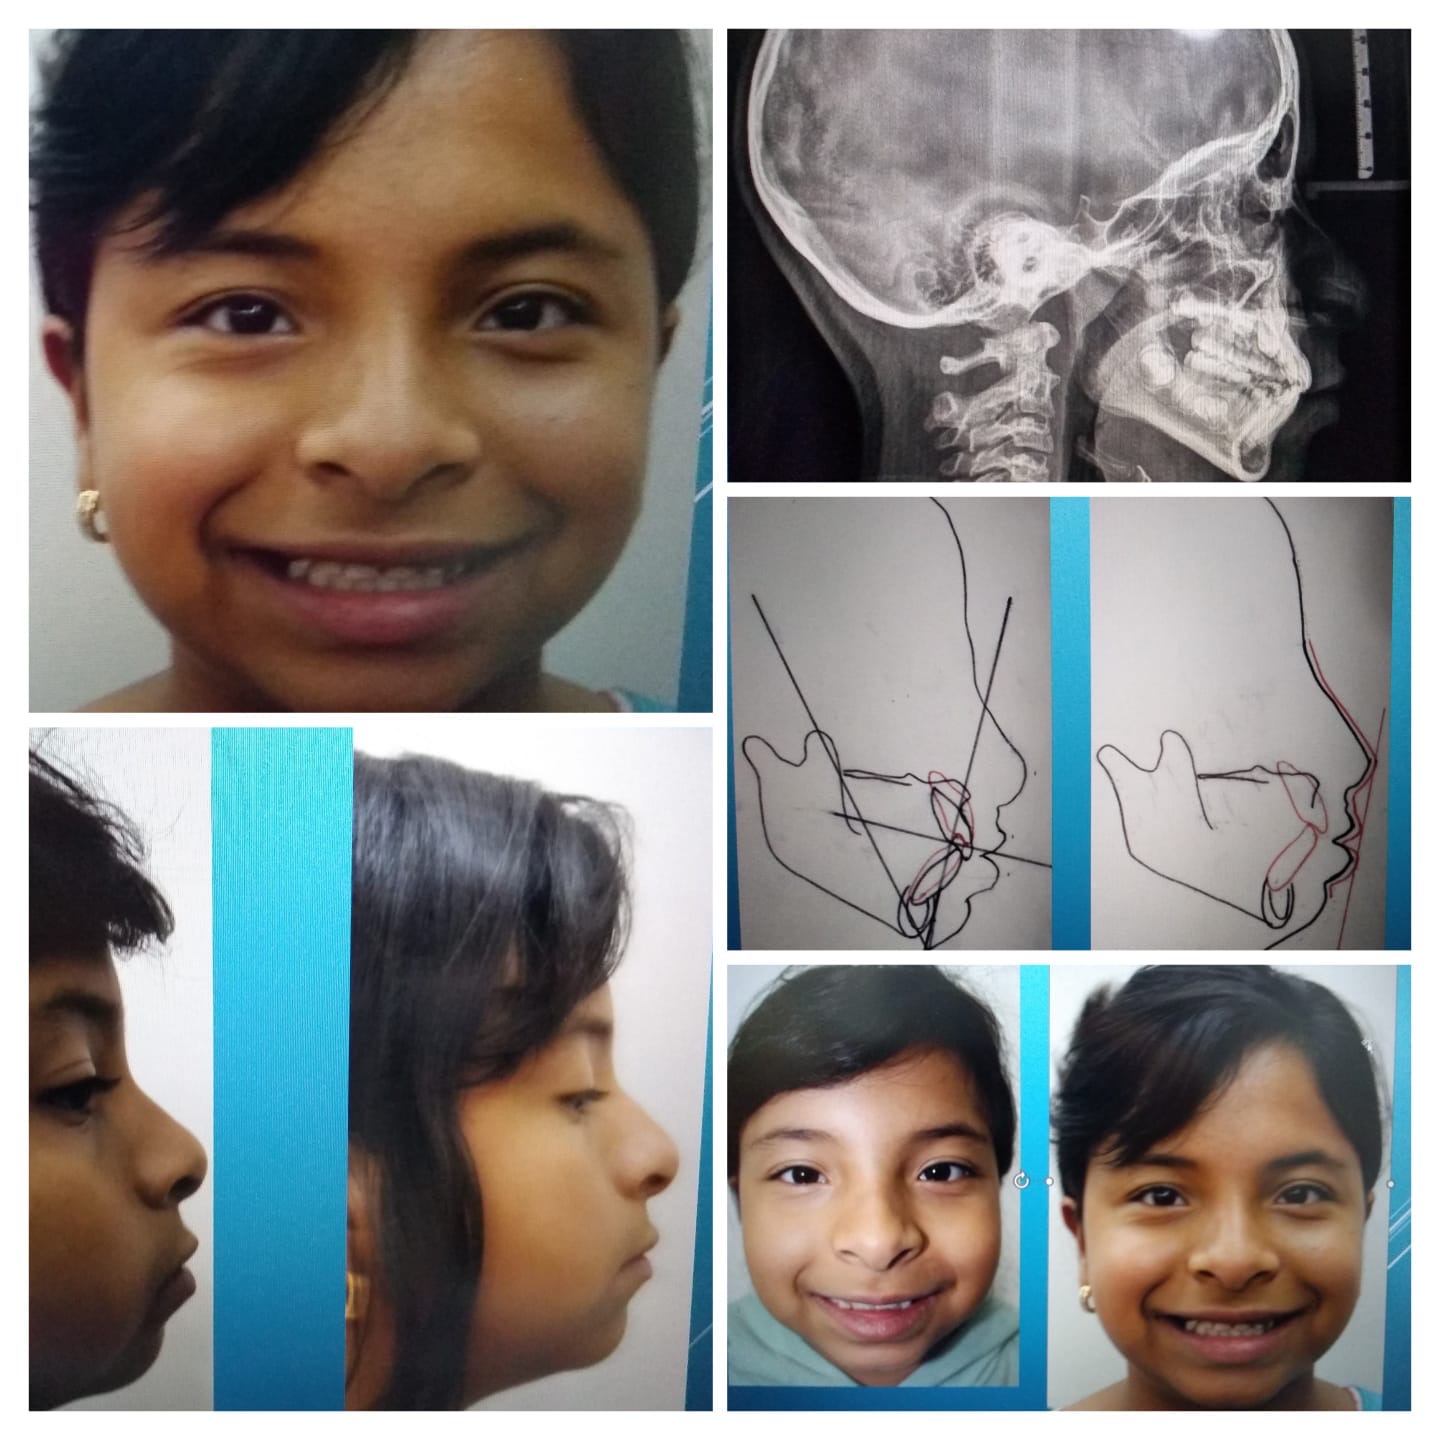

Atendemos ortopedia maxilar para niños y adultos.

En el Consultorio Dental de Alta Especialidad, Ortodoncia y Odontología Infantil brindamos atención especializada a niños y atención en ortopedia maxilar para niños y adultos.

Nuestro enfoque principal está en la atención de pacientes pediátricos, dentro de las áreas de ortodoncia y odontología infantil.

Atención en el área de ortodoncia dentro de un consultorio de alta especialidad.

Atendemos ortopedia maxilar para niños y adultos.